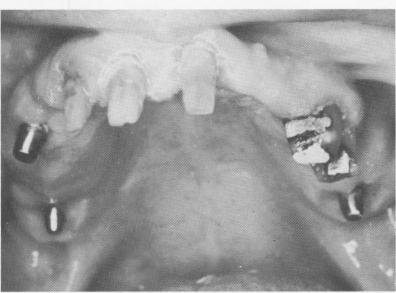

Fig. 11-83. A full arch porcelain-fused-to-metal prosthesis cemented in position.